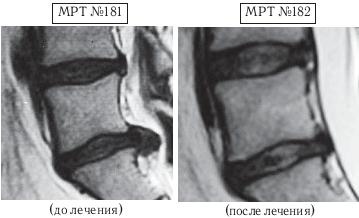

На МРТ № 180 — состояние поясничного отдела позвоночника после лечения методом вертеброревитологии: естественный физиологический лордоз поясничного отдела позвоночника, отсутствие секвестрированной грыжи межпозвонкового диска в сегменте LV—SI, отсутствие стеноза. Но самое интересное можно рассмотреть на МРТ № 181 и МРТ № 182.

На увеличенных фрагментах вышеприведенных снимков наблюдается состояние сегмента LV—SI до лечения (МРТ № 181) и после лечения методом вертеброревитологии (МРТ № 182).

На МРТ № 182 чётко прослеживается не только отсутствие секвестрированной грыжи межпозвонкового диска в сегменте LV—SI но и активный процесс восстановления межпозвонковых дисков (репаративная регенерация) в сегментах LIV—LV, LV—SI, и главное — процесс восстановления их пульпозных ядер. Так что можно образно сказать, что данный парень вытянул в жизни, не без помощи своих родителей, счастливый билет: он уже практически здоров, грыжа диска устранена без операции и биомеханика позвоночника восстановлена, а для молодого организма это немаловажный фактор. Но главное, он получил бесценный, собственный опыт того, что компьютер компьютером, а собственное здоровье ценнее всего и его надо беречь смолоду.